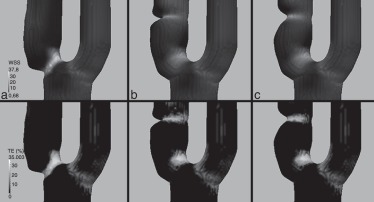

En la figura 7 se muestra el por debajo de 1,5 Pa y el OSI, con el objeto de analizar valores bajos y oscilantes simultáneamente de WSS que puedan ocasionar un riesgo de crecimiento de la placa por HI. Se observa que solo se registran en la parte distal de la estenosis en los modelos B y C. En ambos casos, el riesgo es bajo (no se sitúan claramente por debajo de 0,5 Pa), aunque algo superior en el modelo B que en el C, pues es más oscilante.

Carótidas idealizadas. Arriba: WSS¯ en Pa mostrando solo los valores por debajo ...

Figura 7.

Carótidas idealizadas. Arriba: en Pa mostrando solo los valores por debajo de 1,5 Pa. Abajo: OSI.